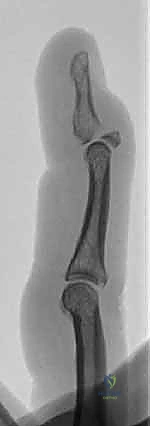

TECH FIG 1 • A With the DIP joint flexed, a K-wire is inserted at the dorsal edge of the articular surface of the middle phalanx.

TECH FIG 1 • B. Bicortical purchase is obtained.

* Technique: "I'm inserting this K-wire obliquely from distal to proximal, aiming to enter the dorsal edge of the articular surface of the middle phalanx. We want bicortical purchase in the middle phalanx. Watch the fluoroscopy screen carefully. We are aiming for the dorsal aspect of the middle phalanx, just proximal to the articular surface, but it's critical that this pin does not engage the fracture fragment itself. Engaging the fragment directly can lead to comminution, which would compromise our reduction and fixation."

* Surgeon's Directive: "Now, with the DIP joint held in this flexed position, we'll insert our first K-wire. This is our dorsal blocking pin. I prefer a 0.045-inch smooth K-wire for most adult digits, though a 0.035-inch might be necessary for smaller fingers. The key here is precision."